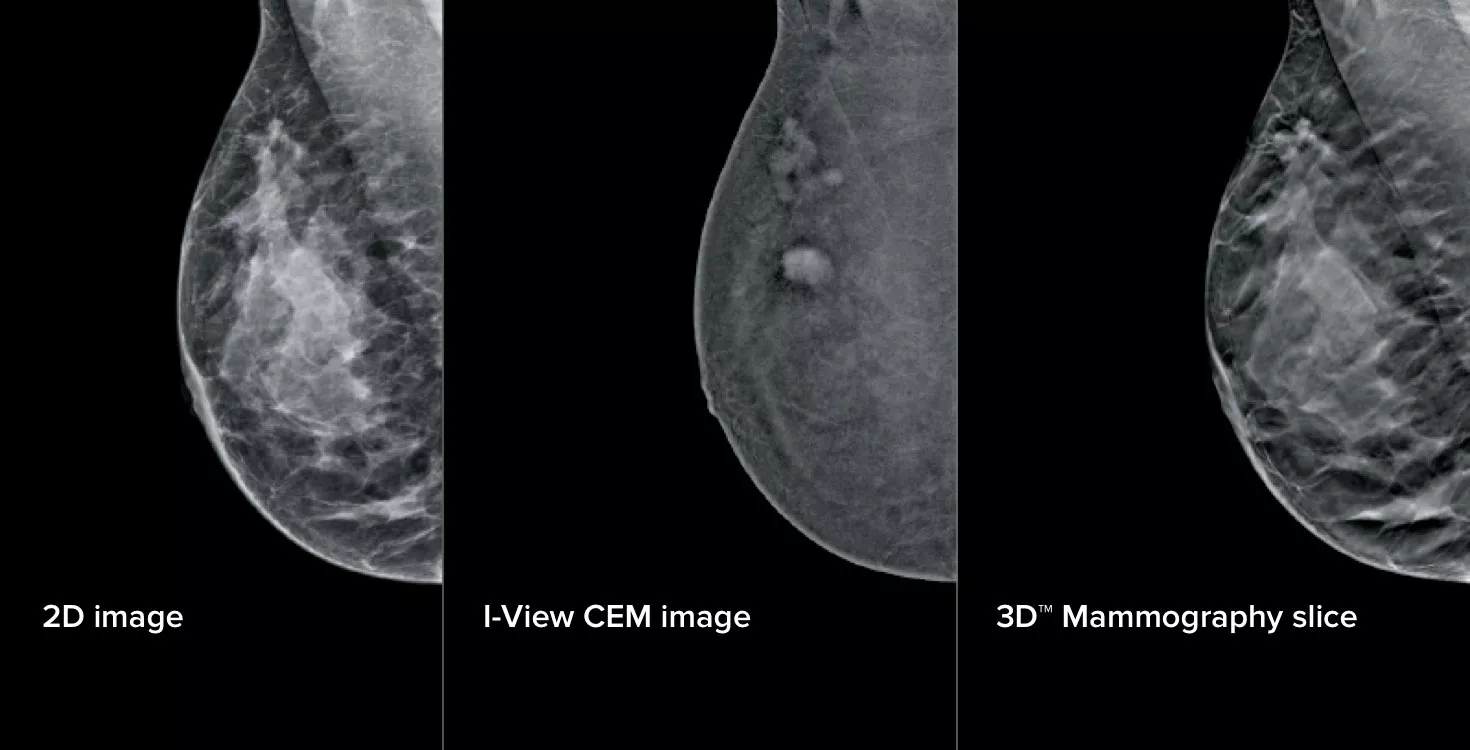

3-in-1 Contrast Enhanced Mammography

Contrast Enhanced Mammography (CEM), the imaging of a breast using iodinated contrast to reveal areas of increased blood supply within the breast, can help enhance suspicious lesions. The I-View software can combine the power of CEM with 2D and tomosynthesis images, all under one compression, providing anatomical and functional imaging in one exam.1

3 Images from 1 Compression

This software captures both anatomical and functional information in a single exam by leveraging our ability to provide 2D, contrast and tomosynthesis images in just one compression.1